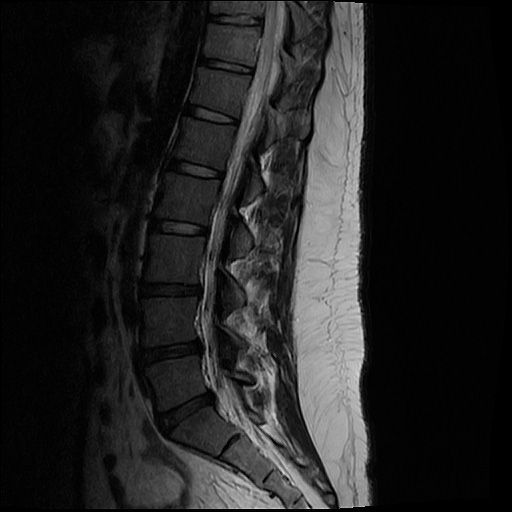

20살 허리디스크 심각한가요?

목디스크 허리디스크 둘다 가지고 있는데 목 몇번이랑 허리 몇번이 터졌고 어느정도 상태인건가요??

올리신 사진들만으로 정확한 디스크 평가가 가능하지는 않습니다. 하지만 사진의 소견들만 보았을 때에는 심하지는 않습니다.

MRI 4컷으로는 디스크 탈출의 정도를 충분히 확인이 불가능합니다.

현재 주어진 사진에서는 허리 디스크는 확인이 가능한 상태이며 그 중등도는 명확히 확인이 어렵습니다.

현재 mri에서는 디스크가 돌출된 부분이 확인됩니다. 디스크가 돌출되었다고 반드시 수술적 치료를 하는 것은 아닙니다. 디스크는 재흡수 되는 경우도 많기에 보존적 치료를 하면서 경과를 보실수 있습니다. 다만 증상이 너무 심하거나 보존적 치료에도 호전이 되지 않는다면 시술이나 수술적 치료를 고려할수 있습니다.